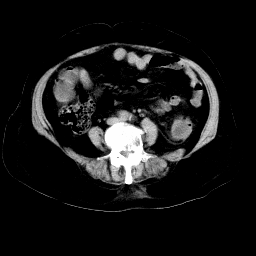

以下是引用arven在2008-11-9 10:13:00的发言:[br]肠壁增厚,形态较规则,支持降结肠炎症改变

以下是引用余辉在2008-11-9 9:47:00的发言:[br]各层面均可见降结肠管壁增厚,管腔狭窄,中部层面可见管壁明显增厚区,结合病史多考虑降结肠癌,溃疡性结肠炎不除外,建议进一步检查